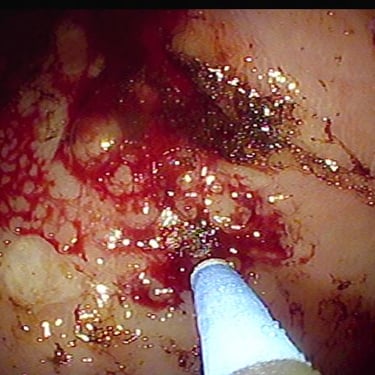

Electrocoagulacion con Argón plasma

Equipo de electrocirugía y electrocagulación con argón plasma inteligente.

Electrocoagulación con Argón plasma en lesiones sangrantes, ulceras, tumores, secuelas de radiacion.

Electrocoagulador inteligente con argón plasma.

Electrocoagulador inteligente con argón plasma

Coagulación con Argón plasma

Telangiectasias intestinales